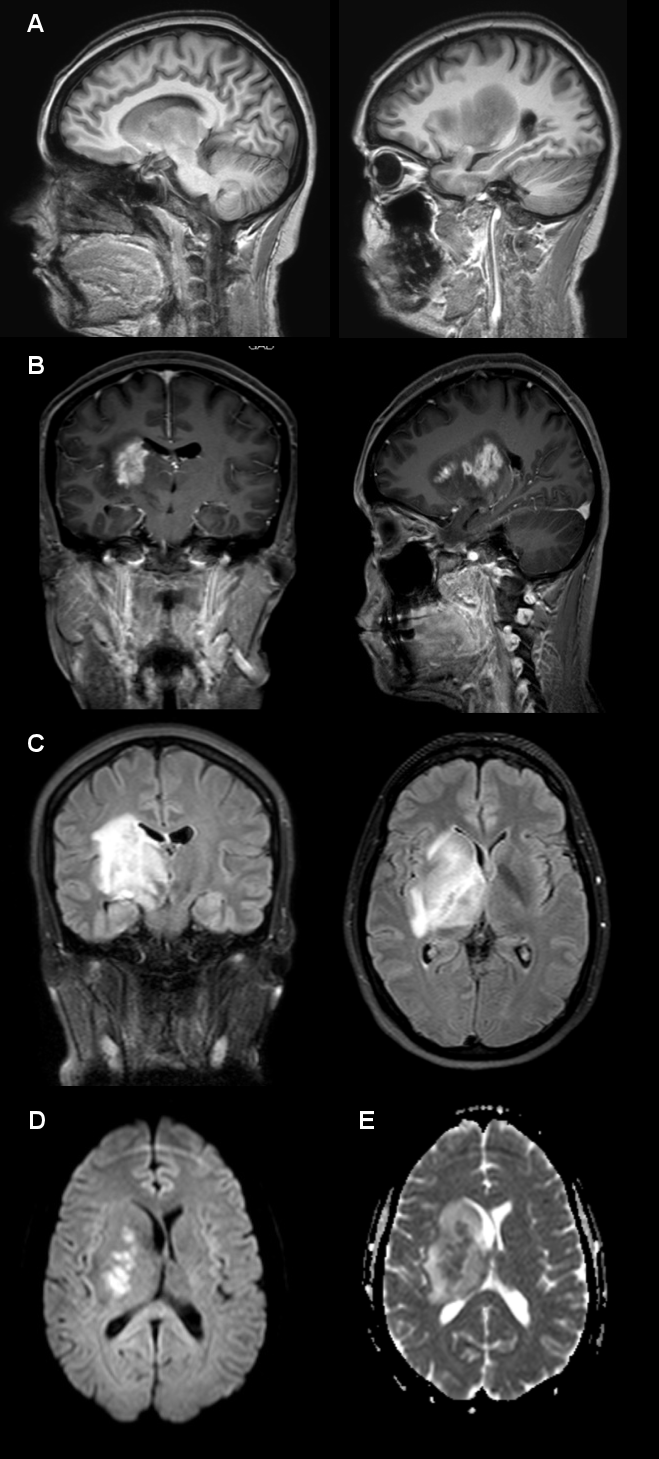

Cranial MRI revealed a large and deep right hemispheric lesion centered at the lenticulo-capsular region that involved the thalamus, the caudate nucleus, the external capsule, subthalamic areas, the right cerebral peduncle and the midbrain, also extending to the radiate crown. It produced a mass effect that deformed the ipsilateral ventricle and deflected the midline structures, disproportionately to its size. After gadolinium administration there was an enhancement of the signal in the center of the lesion; water restriction was also detected in the center of the lesion (FLAIR) (Figure 6 [Fig. 6]). The Angio-MRI was normal.

Figure 6: Cranial MRI. A: before gadolinium. B: after gadolinium: central enhancement is evident. C: FLAIR: periventricular high-signal intensity lesion (coronal and sagital sections). D: Diffusion Weighted (DW): hydric restriction at the center of the lesion. E: Apparent Diffusion Coefficient (ADC): weaker signal.